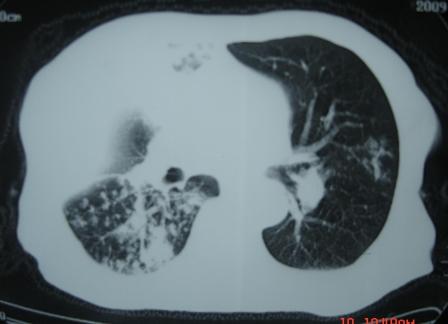

右肺上叶干酪性肺炎并两肺支气管播散。

考虑右肺上叶干酪性肺炎并支气管播散。

楼主  :谢谢大家发言  我和大家考虑的一样干酪性肺炎并播散